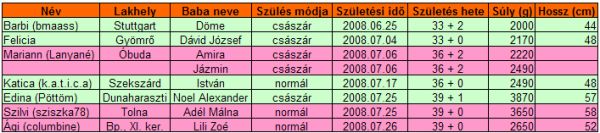

Végre van kis időm bejelentkezni. Köszönjük szépen a gratulációkat és a jókívánságokat, nagyon-nagyon kedvesek vagytok, olyan jól esett! Tényleg!

És én is gratulálok Pöttömnek és Sziszkának is, jó egészséget Nekik!! Olyan jó lesz mostmár, szépen lassan mindenkinek megszületik a kis babája!

Gyorsan rakok fel pár képet, mert azután mennem kell szopiztatni.

Íme a képek: